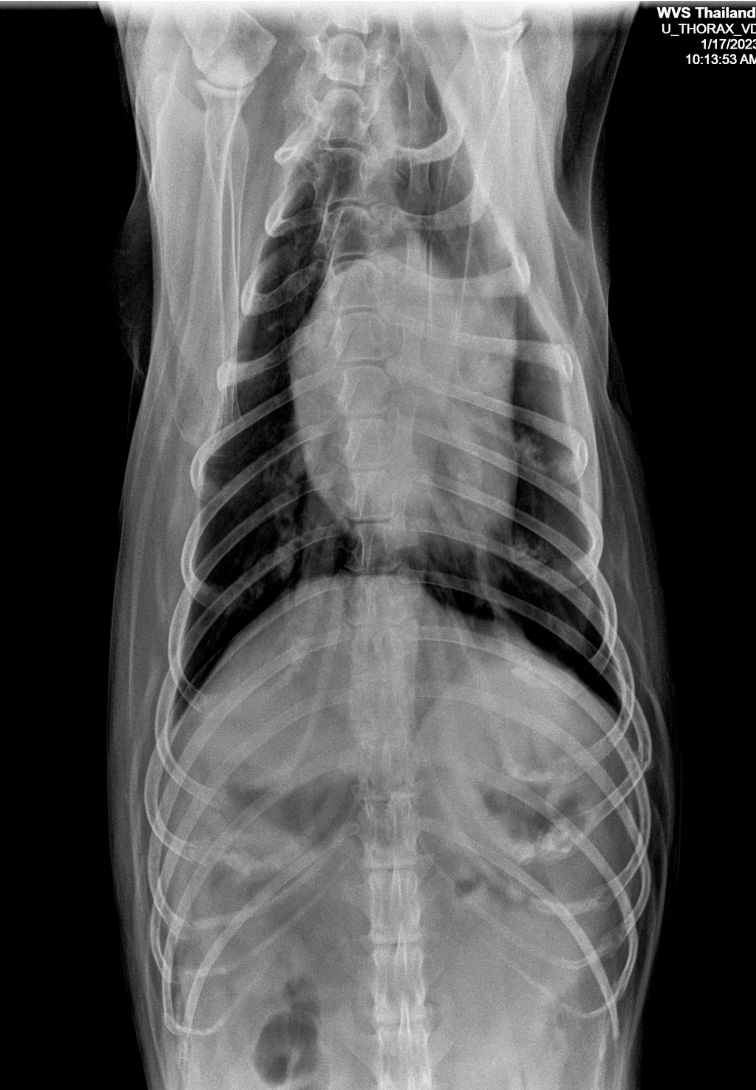

Figure 3 — A low kV image, with high radiographic contrast Radiographic Contrast Positive contrast, negative contrast and neutral contrast. Millions of radiological examinations assisted by intravascular contrast media are conducted each year in north america. Radiographic contrast is the density difference between neighboring regions on a plain radiograph. Understanding the image creation process as it relates to the interplay of contrast, noise, patient dose, and diagnostic performance is vital in the practice. Radiographic Contrast.